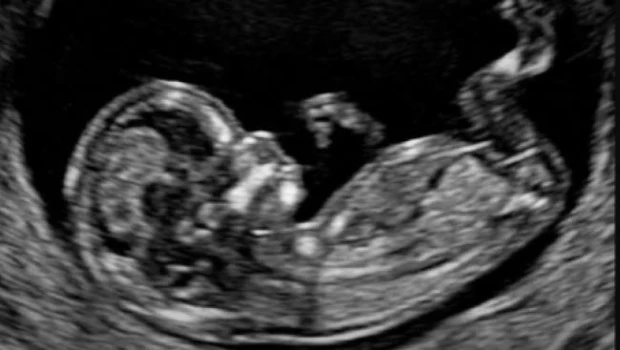

De esa manera, el niño por nacer queda exactamente en ese lugar incómodo que la sociedad prefiere no mirar. No tiene voz, no tiene representación y en muchos casos, ni siquiera es reconocido como sujeto.

Se habla de derechos, de protección y de infancia, pero se hace una excepción silenciosa justo en el inicio. Y esa excepción no es menor: define quién entra en la comunidad de los que importan y quién puede quedar afuera sin demasiadas preguntas.

Por eso cada 25 de marzo no debería pasar desapercibido. No es solo una conmemoración. Es un llamado incómodo pero necesario: recordar que hay una vida que no tiene voz, pero sí valor; que no tiene lugar en el debate, pero sí existencia. Y que una sociedad se define, en última instancia, no por las excepciones que permite, sino por las vidas que decide proteger.